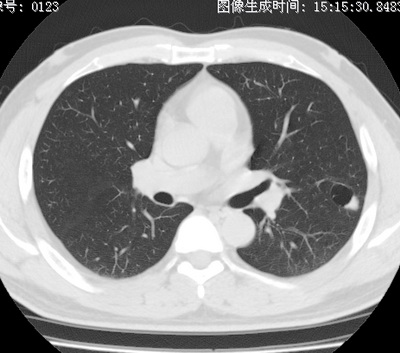

以下是引用zhao_bin2008在2010-1-4 20:15:00的发言:[br]先天性肺囊肿或小的肺隔离症?

以下是引用卜一在2010-1-4 22:09:00的发言:[br]先天性肺囊肿或小的肺隔离症?支持!

以下是引用zsl6918在2010-1-5 5:23:00的发言:[br]良性改变!肺囊肿,先天性支气管闭锁,血管畸形等均有可能。

以下是引用影像之路在2010-1-6 11:10:00的发言:[br]腺癌,最终的病检有些出乎意料之外,术前同志们大多考虑为肺囊肿或小的肺隔离征 [br]回过头来看 小结节呈分叶状,其内侧有一条较粗的静脉供血或许能成为支持诊断腺癌的理由